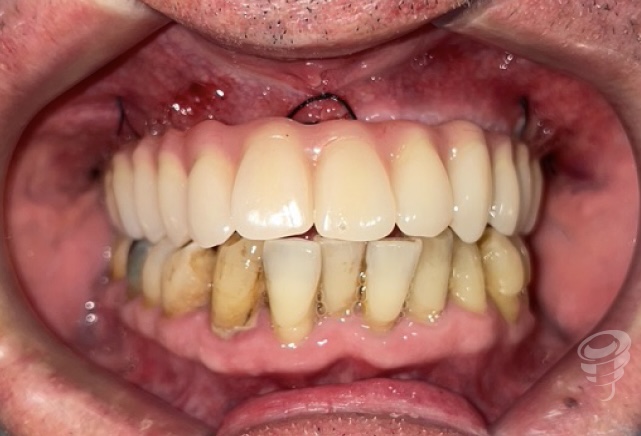

Imagen 22 – Prótesis de carga inmediata

Imagen 23 – Oto Postop Inmediato

Imagen 24 – Carga Inmediata

Imagen 25 – Carga Inmediata